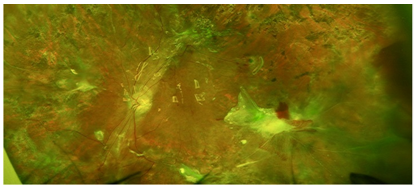

Surgical Management of Posterior and Retracted Retinal Breaks with Amniotic Membrane Plugs: A Case Series

MD Najib Arsalan, PHD Muraine Marc and MD Lorenzi Umberto. 15(07): 01-07.